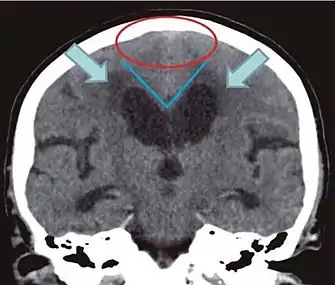

- Imaging from magnetic resonance imaging (MRI) or computed tomography (CT) is needed to demonstrate enlarged ventricles and no macroscopic obstruction to cerebrospinal fluid flow. Imaging should show an enlargement to at least one of the temporal horns of lateral ventricles, and impingement against the falx cerebri resulting in a callosal angle ≤ 90° on the coronal view, showing evidence of altered brain water content, or normal active flow (which is referred to as "flow void") at the cerebral aqueduct and fourth ventricle.

| Normal pressure hydrocephalus | Brain atrophy | |

|---|---|---|

| Preferable projection | Coronal plane at the level of the posterior commissure of the brain. | |

| Modality in this example | CT | MRI |

| CSF spaces over the convexity near the vertex (red ellipse | Narrowed convexity ("tight convexity") as well as medial cisterns | Widened vertex (red arrow) and medial cisterns (green arrow) |

| Callosal angle (blue V) | Acute angle | Obtuse angle |

| Most likely cause of leucoaraiosis (periventricular signal alterations, blue arrows |

Transependymal cerebrospinal fluid diapedesis | Vascular encephalopathy, in this case suggested by unilateral occurrence |